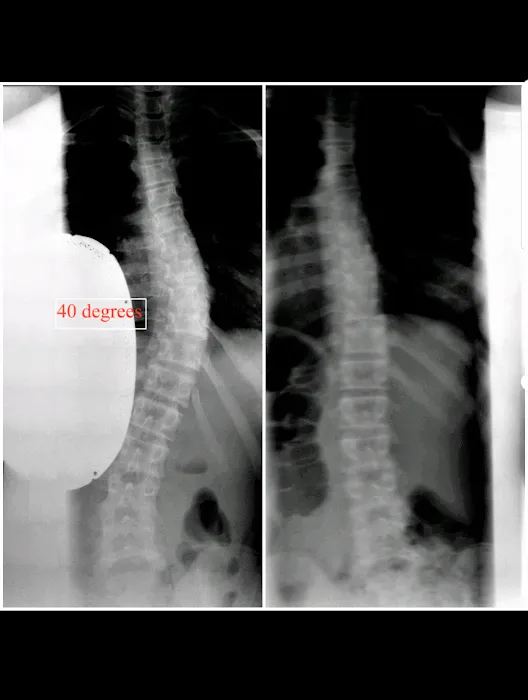

Chiropractic is a healthcare discipline focused on the diagnosis, treatment, and prevention of musculoskeletal disorders, especially those affecting the spine. The foundational principle is that proper alignment of the body's structure, particularly the spine, enables the body to heal itself without surgery or excessive medication. Chiropractors, like Dr. Kang, utilize hands-on techniques, primarily spinal adjustments, to correct misalignments (often called subluxations) that can interfere with the nervous system, leading to pain, reduced mobility, and other health issues. What sets the New York Chiropractic & Scoliosis Center apart is its specialized focus on scoliosis, a condition involving abnormal curvature of the spine. For New Yorkers dealing with the challenges of scoliosis-related pain or other chronic spinal conditions, having access to a center with dedicated expertise in this area is invaluable.

- Scoliosis Correction and Management: Specialized techniques and personalized treatment plans aimed at reducing the progression of scoliosis, alleviating pain, and improving spinal alignment for patients of all ages.

- Comprehensive Spinal Analysis: Thorough evaluation, including possibly advanced diagnostic tools, to accurately assess the patient's spinal condition and tailor treatment.

- Scoliosis Specialization: A distinct advantage is their dedicated expertise in treating scoliosis, offering hope and relief to those with this challenging condition.